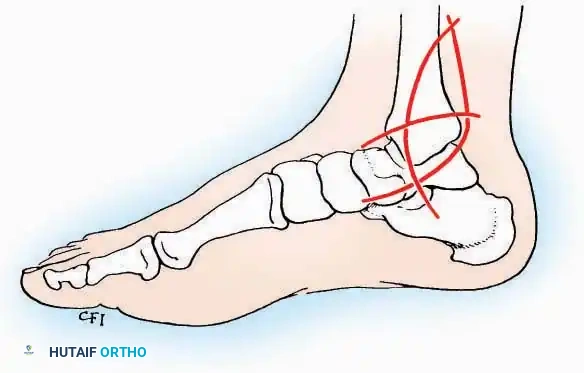

SURGICAL APPROACHES TO THE CALCANEUS

Approaches to the calcaneus are dictated by the pathology—trauma (intra-articular fractures) versus tumor/infection. Positioning is critical; while the prone position offers excellent bilateral access, the lateral decubitus or modified supine positions are more frequently utilized for unilateral trauma.

Lateral Approach (Extensile Lateral)

This is the workhorse approach for open reduction and internal fixation (ORIF) of displaced intra-articular calcaneal fractures.

Indications: ORIF of calcaneus fractures, lateral wall exostectomy, subtalar arthrodesis.

Positioning: Lateral decubitus with the operative leg up, or supine with a large bump under the ipsilateral hip to internally rotate the leg.

Surgical Technique:

* Incision: Begin the incision on the lateral margin of the Achilles tendon near its insertion. Extend it distally to a point 4 cm inferior and 2.5 cm anterior to the lateral malleolus. (For trauma, a classic L-shaped extensile incision is often used, dropping straight down anterior to the Achilles, then curving gently toward the base of the 5th metatarsal).